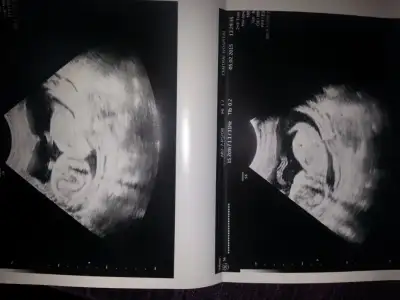

dr soylemeden siz gorun genital nub teorisi ( bebegin cinsiyeti)

gulsennn 2.ci resim tam net çıkacakmış ama nubu yarım kalmış :)))) sanki kız o gördüğüm nub ise paralel gibi

Canim ikinci resimde bağdaş kurduğu için minik bebeğim orası öyle :) hayırlısı olsun inşallah teşekkür ederim

Gulsennnn senin daha cok erken bu eklediğin foto 9 haftalık nub icin 11-12-13 haftalar ultrason olması daha saglikli olur pek belli olmuyor

bende paralel gibi gördüm ikinci resimde hayırlı olsunAaa oldu becerdim banada yorum yapar misiniz

Gulsennnn senin daha cok erken bu eklediğin foto 9 haftalık nub icin 11-12-13 haftalar ultrason olması daha saglikli olur pek belli olmuyor

Tamam canım ctesi 12+5 olucam özel dr gideceğim bakalım görecek mi cinsiyetini çok teşekkür ederim Allah razi olsun

Bencede kiz canim :)

erkekAaa oldu becerdim banada yorum yapar misiniz

Doktorlar emin olmadıkları için söylemiyorlar erkek oranıyla kız organı birbirine benziyo aonradan erkeğinki uzuyo bayanınki şekilleniyor. Pozisyonda duruma yatıışına göre değiştiği için hemen söylemiyolar doktorlar.

Ben de resmi yükleyemedim telefondan ama baktigim zaman kiz orasi paralel peki kesin sonuc mu doktorlar neden soylemiyorlar